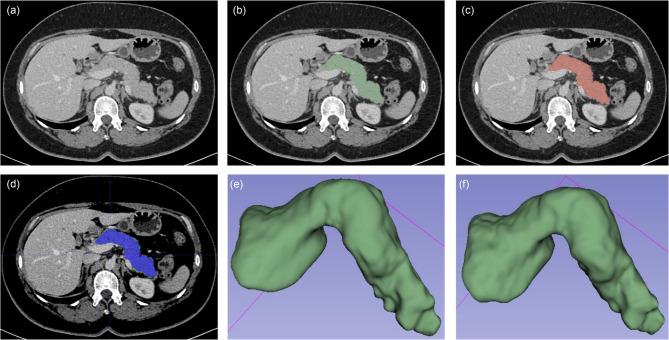

Accurate and fully automated pancreas segmentation is critical for advancing imaging biomarkers in early pancreatic cancer detection and for biomarker discovery in endocrine and exocrine pancreatic diseases. We developed and evaluated a deep learning (DL)-based convolutional neural network (CNN) for automated pancreas segmentation using the largest single-institution dataset to date (n = 3031 CTs). Ground truth segmentations were performed by radiologists, which were used to train a 3D nnU-Net model through five-fold cross-validation, generating an ensemble of top-performing models. To assess generalizability, the model was externally validated on the multi-institutional AbdomenCT-1K dataset (n = 585), for which volumetric segmentations were newly generated by expert radiologists and will be made publicly available. In the test subset (n = 452), the CNN achieved a mean Dice Similarity Coefficient (DSC) of 0.94 (SD 0.05), demonstrating high spatial concordance with radiologist-annotated volumes (Concordance Correlation Coefficient [CCC]: 0.95). On the AbdomenCT-1K dataset, the model achieved a DSC of 0.96 (SD 0.04) and a CCC of 0.98, confirming its robustness across diverse imaging conditions. The proposed DL model establishes new performance benchmarks for fully automated pancreas segmentation, offering a scalable and generalizable solution for large-scale imaging biomarker research and clinical translation.

准确且完全自动化的胰腺分割对于推进早期胰腺癌检测中的成像生物标志物以及内分泌和外分泌胰腺疾病的生物标志物发现至关重要。我们使用迄今为止最大的单机构数据集(n = 3031例CT)开发并评估了一种基于深度学习(DL)的卷积神经网络(CNN)用于自动化胰腺分割。由放射科医生进行真实分割,通过五折交叉验证用于训练3D nnU-Net模型,生成一组表现最佳的模型。为了评估泛化能力,该模型在多机构的AbdomenCT-1K数据集(n = 585)上进行了外部验证,专家放射科医生新生成了该数据集的体积分割并将公开提供。在测试子集(n = 452)中,CNN实现了0.94(标准差0.05)的平均骰子相似系数(DSC),表明与放射科医生标注的体积具有高度空间一致性(一致性相关系数[CCC]:0.95)。在AbdomenCT-1K数据集上,该模型实现了0.96(标准差0.04)的DSC和0.98的CCC,证实了其在不同成像条件下的稳健性。所提出 的DL模型为完全自动化胰腺分割建立了新的性能基准,为大规模成像生物标志物研究和临床转化提供了一种可扩展且可泛化的解决方案。